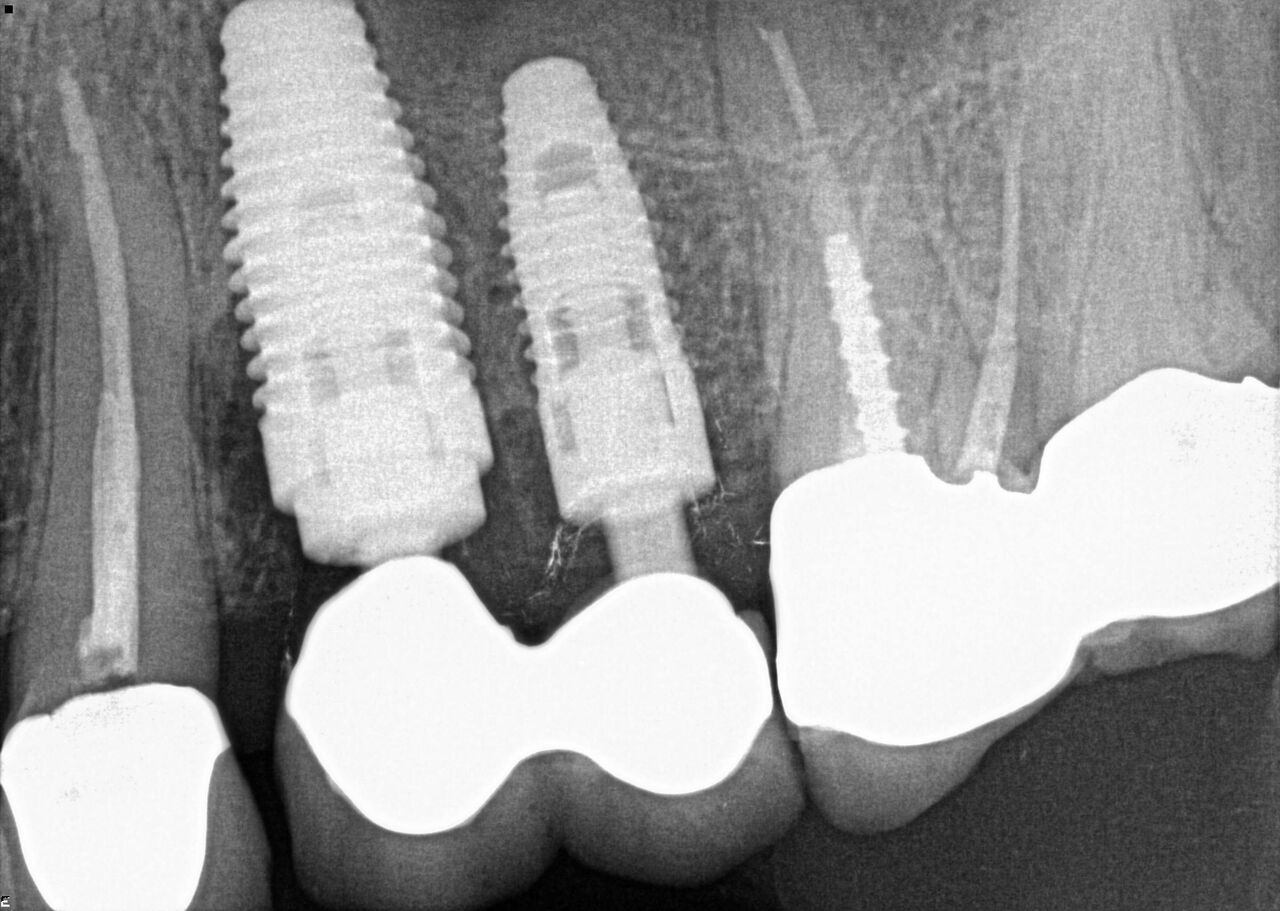

(16.) Radiograph of final restorations on Nos. 12 and 13. Notice platform shift in No. 12 restoration.

Figure 16

The patient was prescribed antibiotics and analgesics and instructed in postoperative care particular to immediately provisionally restored implants. At 6 months, integration was confirmed (Figure 14) and the patient returned to her dentist for restoration. The implants were restored with individual cement-retained crowns with a platform shift for No. 12 restoration from the 6-mm diameter of the implant to a 5-mm diameter of the final restoration (Figure 15 and Figure 16).